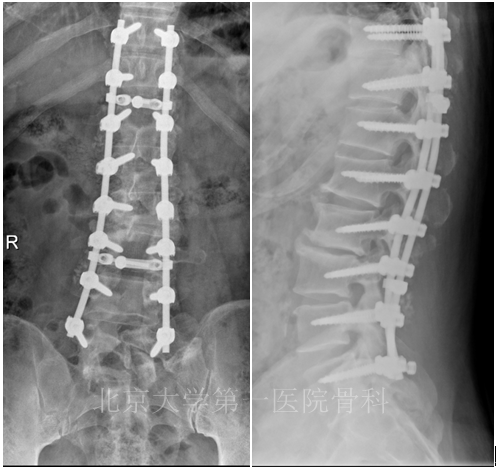

术前诊断:1.腰椎退变性侧凸;2.腰椎滑脱(L2、退变性、I度);3.高血压病;4.帕金森病。行T10-L5长节段手术,术后1个月L5螺帽松动。

术后18个月患者重新就诊,主诉左下肢疼痛6个月。 术后腰部轻度疼痛。6月前无明显诱因出现左下肢疼痛,沿左侧臀部、大腿外侧至小腿后外侧,伴有麻木感。腰痛VAS评分3分,左下肢VAS评分5分。背部可见原手术切口愈合良好,腰椎活动度减弱。L5水平叩痛(+)。四肢肌张力略高,可见不自主震颤。双下肢感觉、肌力、反射对称。双侧直腿抬高试验(-),双侧股神经牵拉试验(-)。

患者行翻修手术治疗,L4/5短节段翻修。目前随访6个月以上,患者图特殊不适。

专家点评:螺帽的松动,是由于手术原因,还是因为患者自身帕金森病导致的螺帽松动?目前不得而知,但对待合并帕金森病的要慎重,手术节段要慎重选择。